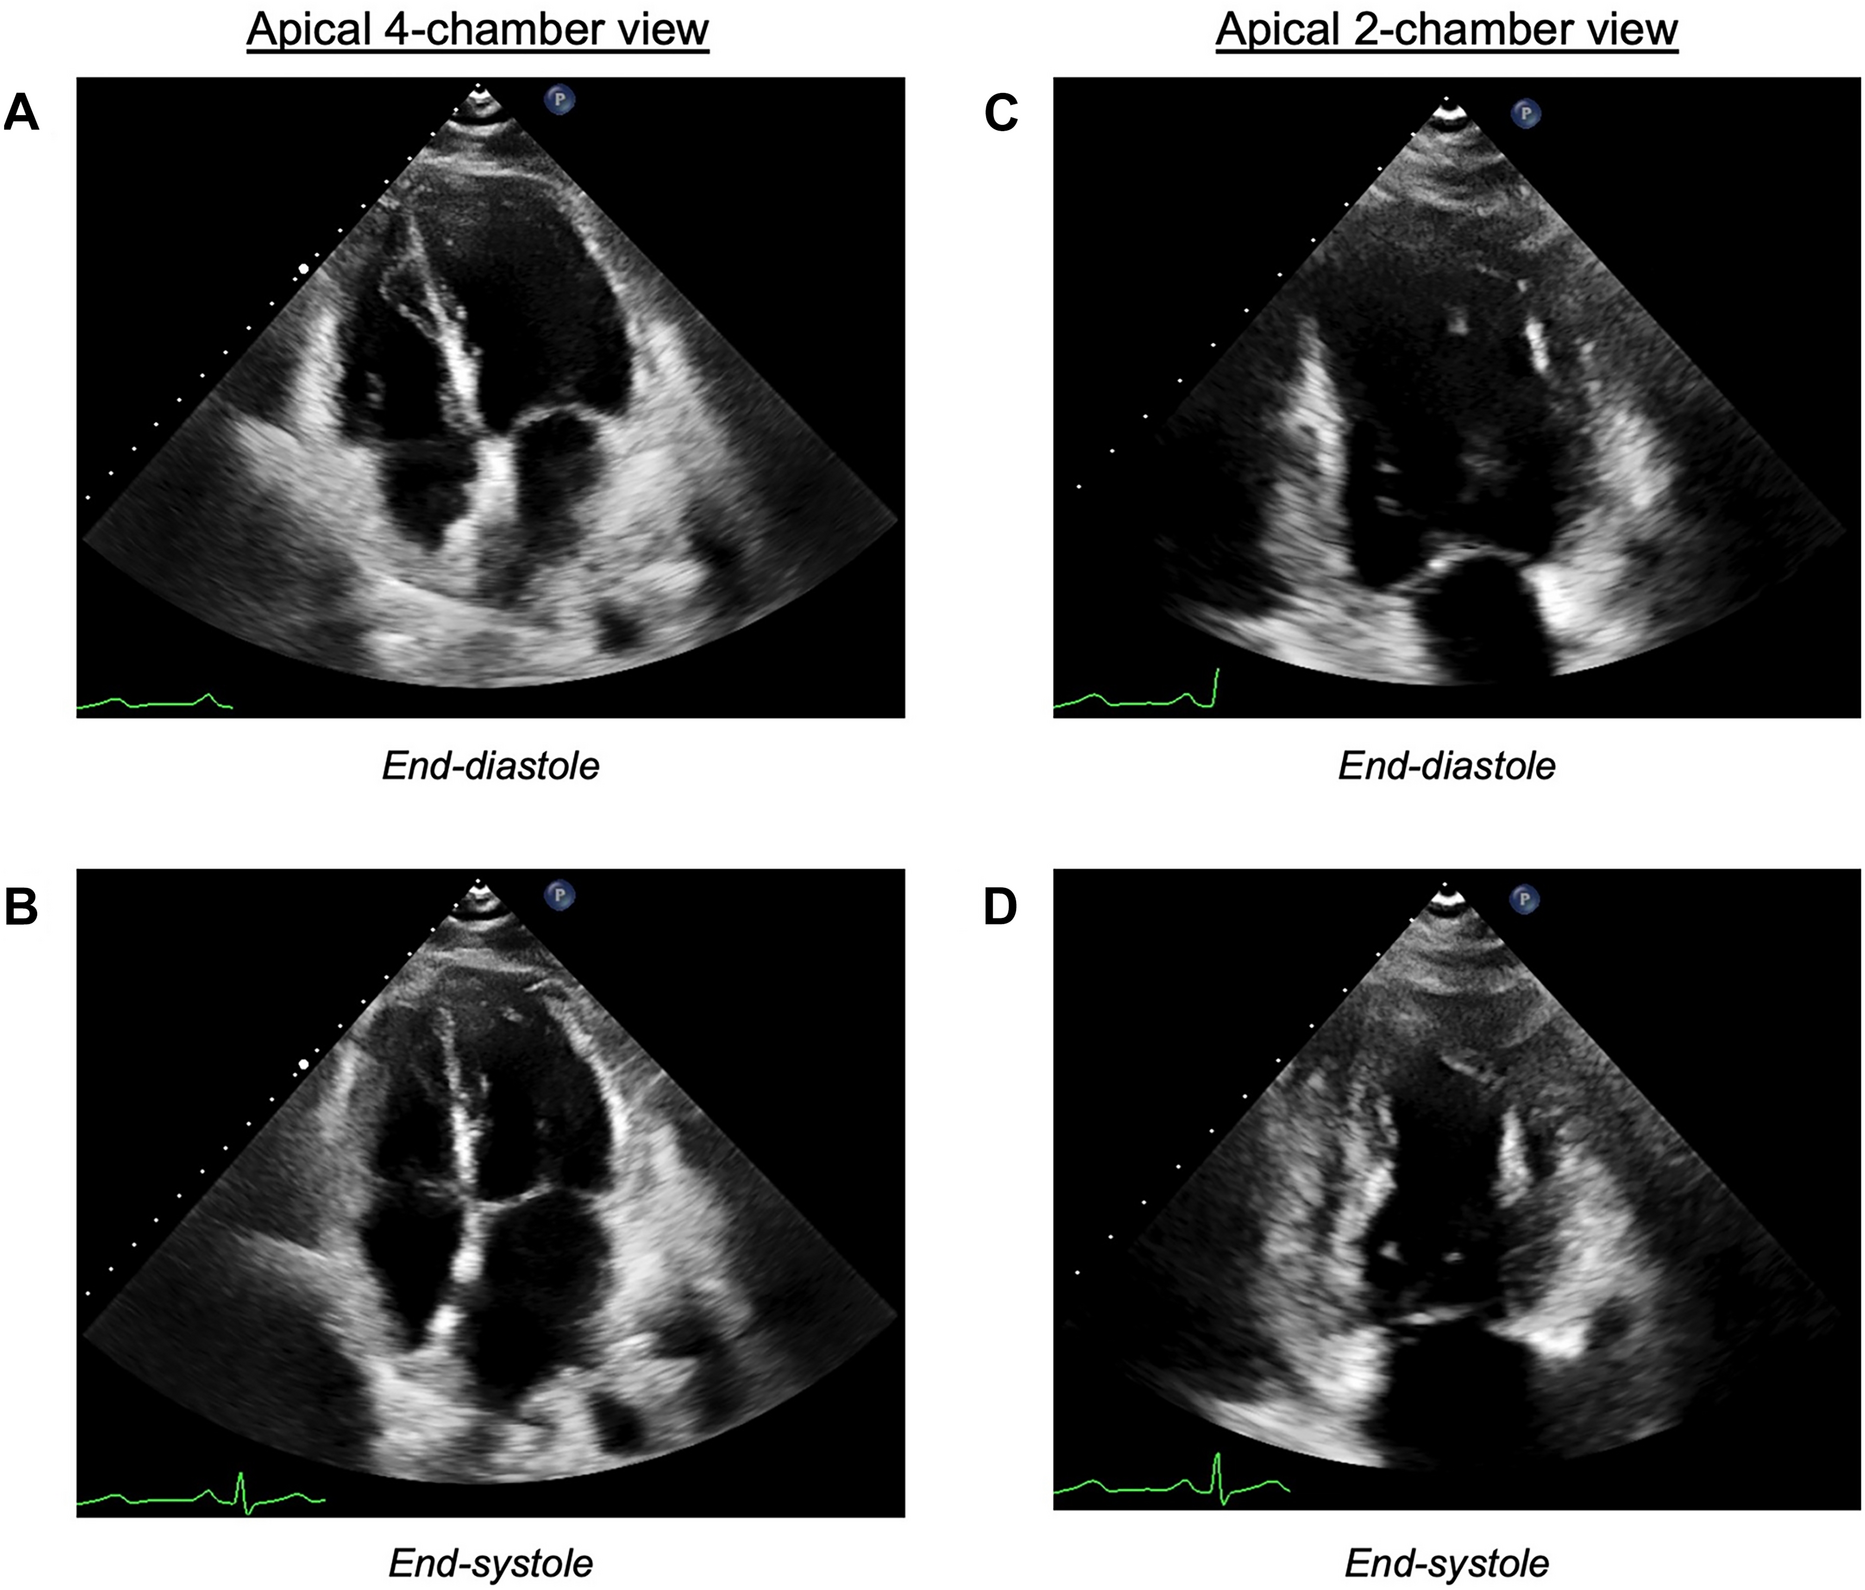

Fig. 3

Transthoracic echocardiogram obtained 4.5 h after the initial epinephrine bolus. Representative images from the apical four-chamber view are shown at A end-diastole and B end-systole. Representative images from the apical two-chamber view are shown at C end-diastole and D end-systole. Relative to Fig. 2, increased contractility is visualized in the mid- and basal segments of the left ventricle. E Polar plot of the longitudinal strain mapping derived from this echocardiogram, illustrating basal-predominant hypokinesis with relative apical sparing

A transthoracic echocardiogram (TTE) obtained 4.5 h after the intraoperative TEE showed persistent global hypokinesis with left ventricular apical sparing but improvement in the LVEF to 30–35% (Fig. 3, Videos 3 and 4). Right heart catheterization revealed severely elevated right- and left-sided filling pressures with a preserved cardiac index (Table 1) on 5 mcg/min epinephrine, 120 mcg/min phenylephrine, and 0.05 mcg/kg/min epoprostenol. Invasive coronary angiography demonstrated no obstructive coronary artery disease or spontaneous coronary vasospasm. Provocative testing for coronary vasospasm was not performed. The patient underwent diuresis with an intravenous furosemide infusion. Given concern for a distributive component to the patient’s shock (Table 1) and worsening lactic acidosis to 7.4 mmol/L, the patient was started on stress-dose hydrocortisone, vancomycin, cefepime, and metronidazole. The vasopressors were cross-titrated from epinephrine and phenylephrine to norepinephrine.

Video 3: Apical four-chamber view from the transthoracic echocardiogram obtained 4.5 hours after the initial epinephrine bolus. Still images from this view are reproduced in Fig. 3A and 3B (MP4 23773 KB)

Video 4: Apical two-chamber view from the transthoracic echocardiogram obtained 4.5 hours after the initial epinephrine bolus. Still images from this view are reproduced in Fig. 3C and 3D (MP4 26501 KB)